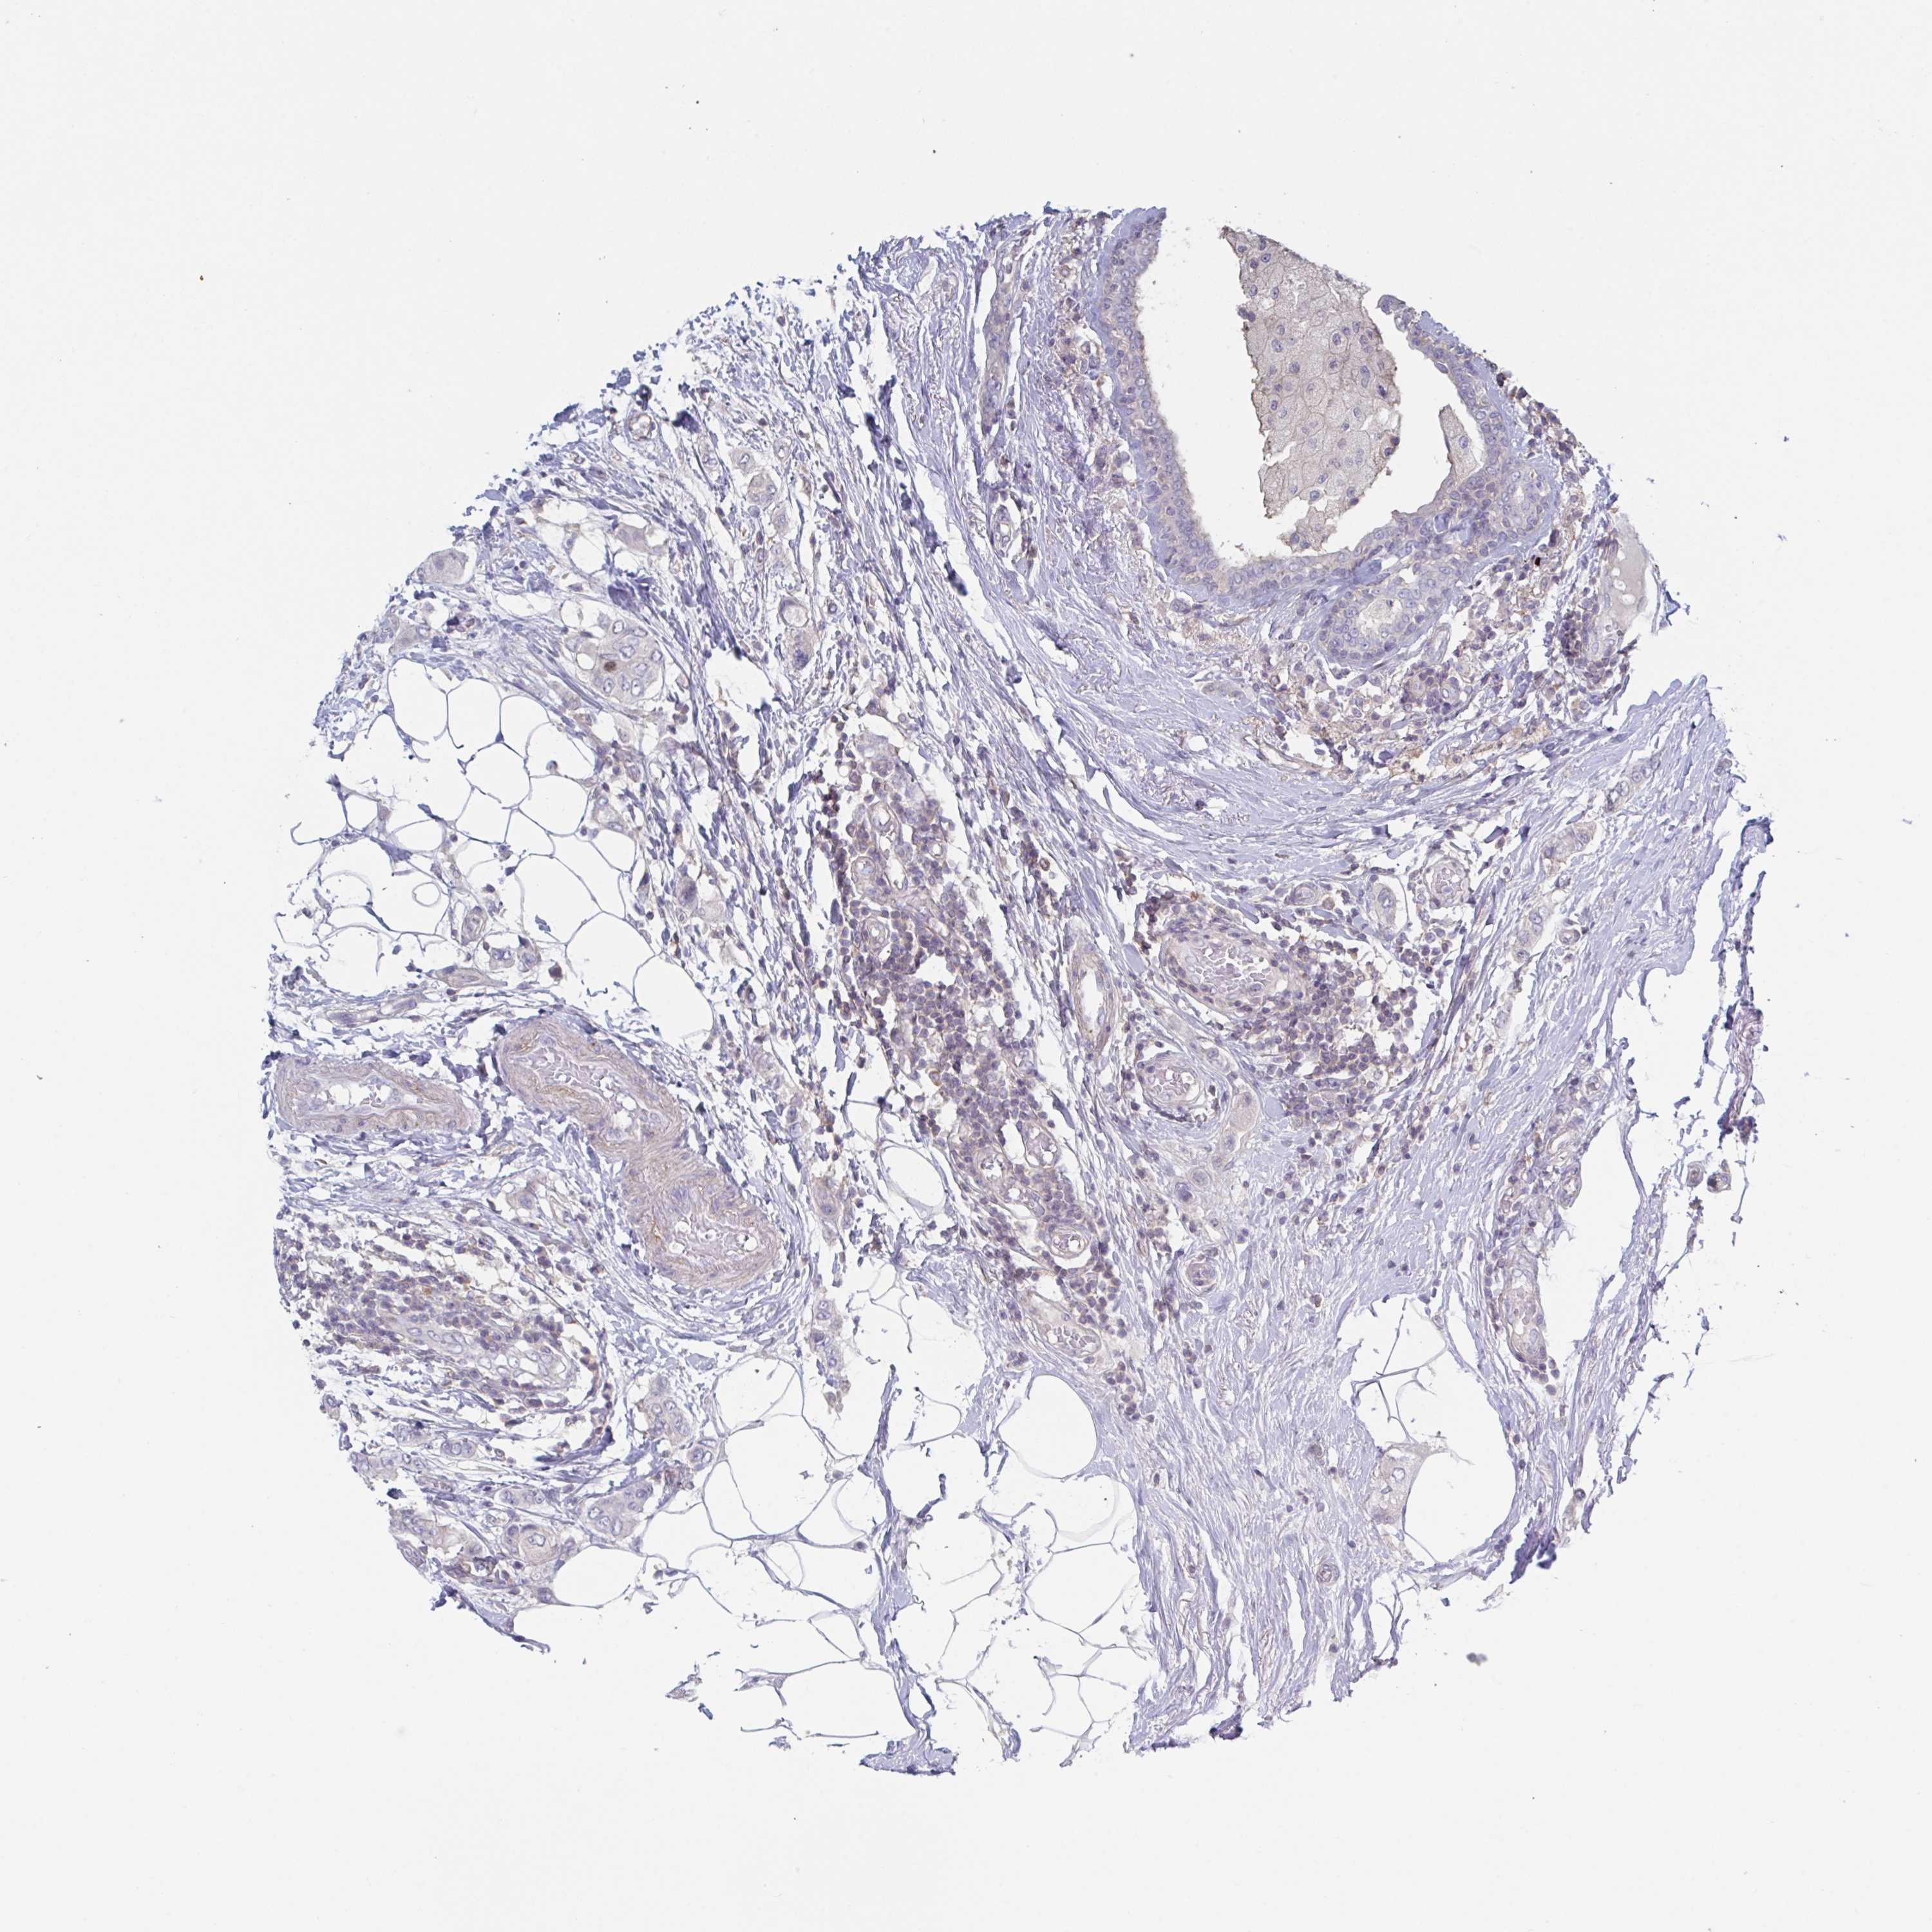

BRCA TCGA BRCA VALIDATION PROTEIN EXPRESSION